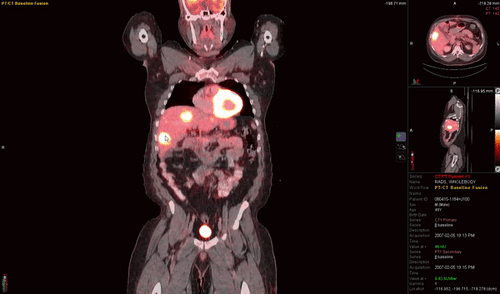

Advanced Therapy Response

LesionID® Pro and PET Edge®+ allow you to provide referring physicians with the latest clinically-significant staging and therapy response information, such as SUVmean, SUV Peak, and Total Metabolic Tumor Volume.